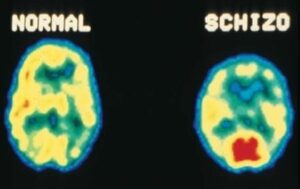

Um surto psicótico com delírios e alucinações que distorcem a realidade e a pessoa esquizofrênica é mal compreendida e apontada